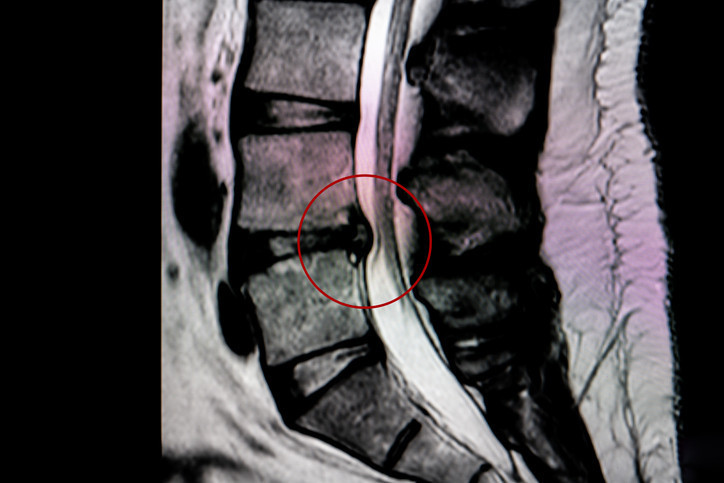

Kauda equina sendromu, omurganın alt bölümündeki sinir demetinin baskı altında kalmasıyla ortaya çıkan nadir ama çok ciddi bir nörolojik acil durum olarak tanımlanıyor. Bu sinirler bacak hareketlerini, his kaybını, mesane ve bağırsak kontrolünü etkilediği için tablo ilerlediğinde kalıcı hasar bırakabiliyor. Uzmanlara göre hastalık tedavi edilmez ya da müdahale gecikirse kalıcı idrar-dışkı kontrol kaybı, cinsel işlev bozukluğu ve bacaklarda felç gelişebiliyor.

Hastalığın en sinsi tarafı, bazen ilk etapta sıradan bir bel fıtığı ya da şiddetli bel ağrısı gibi başlayabilmesi. En yaygın nedenlerden biri alt bel bölgesindeki büyük disk fıtıkları. Bunun dışında travma, omurga darlığı, tümör, enfeksiyon, doğumsal sorunlar ve bazı ameliyat komplikasyonları da tabloyu tetikleyebiliyor.

Bu sendromda zamanla yarışılıyor. Uzmanlar, tanı konduktan sonra sinirler üzerindeki baskının mümkün olan en kısa sürede kaldırılması gerektiğini, ilk 24-48 saatin büyük önem taşıdığını belirtiyor. Tedavi çoğu zaman acil cerrahiyle yapılıyor. Amaç, sinirler üzerindeki basıyı kaldırıp kalıcı hasarı önlemek. Gecikme olduğunda iyileşme şansı düşebiliyor ve bazı hastalarda kalıcı nörolojik sorunlar kalabiliyor.

Kauda equina sendromu nadir görülse de, sonuçları nedeniyle doktorların özellikle dikkat çektiği hastalıklardan biri. Çünkü mesele yalnızca şiddetli bel ağrısı değil; sinir sisteminin alt bölümünü ilgilendiren bir sıkışma olduğu için geri dönüşü zor tablolar ortaya çıkabiliyor.